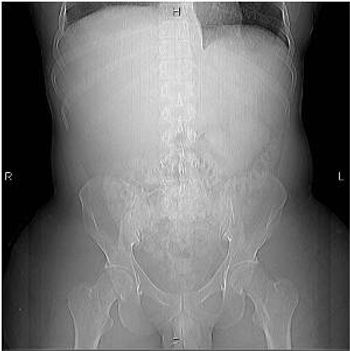

A 31-year-old male, recently on active duty in the military, presents to the ER with approximately one- week history of abdominal bloating, early satiety, and back pain. The patient has recently returned from overseas duty in Iraq, but otherwise has had no other significant travel history. On specific questioning, the patient reports he has “probably been exposed to toxic chemicals.” The patient is otherwise in healthy condition, and denies recent surgery, or illness, and takes no medication. He admits to social alcohol use only, and denies IV drug abuse.